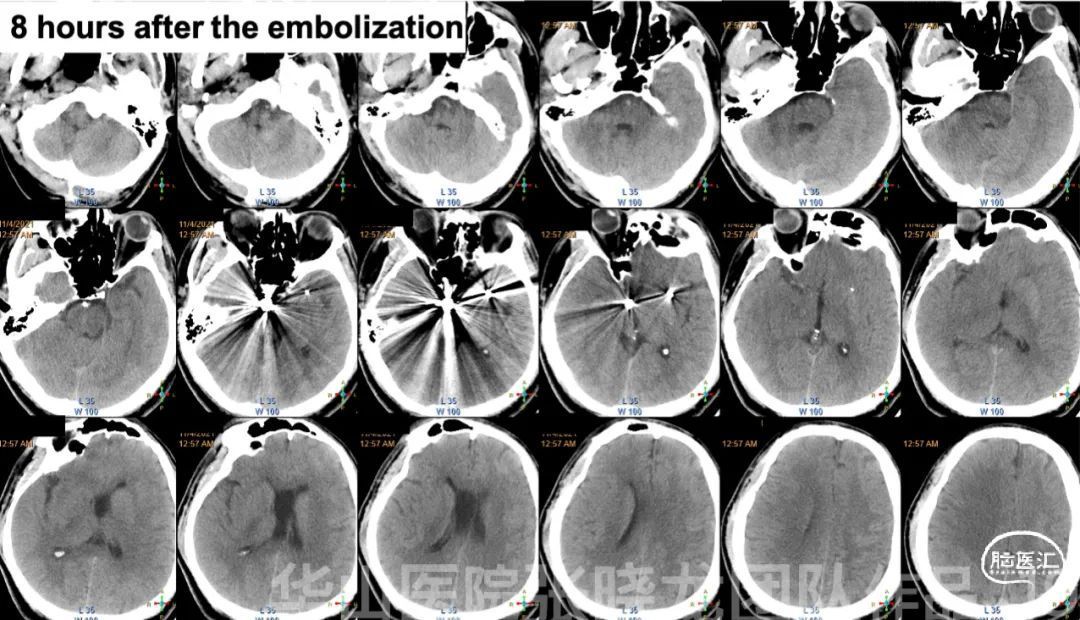

图 19. 立即行头颅CT,未见出血。予半量肝素化。

Figure 21. Post-operative day 2 head CT showed no hemorrhage and DWI depicted right cerebellum, midbrain and left basal ganglia region acute infarction with bilateral hemisphere scattered infarction.

图 21. 术后第2天头颅CT未见出血,DWI提示右侧小脑半球、中脑及左侧基底节区急性脑梗,双侧大脑半球散在梗死。